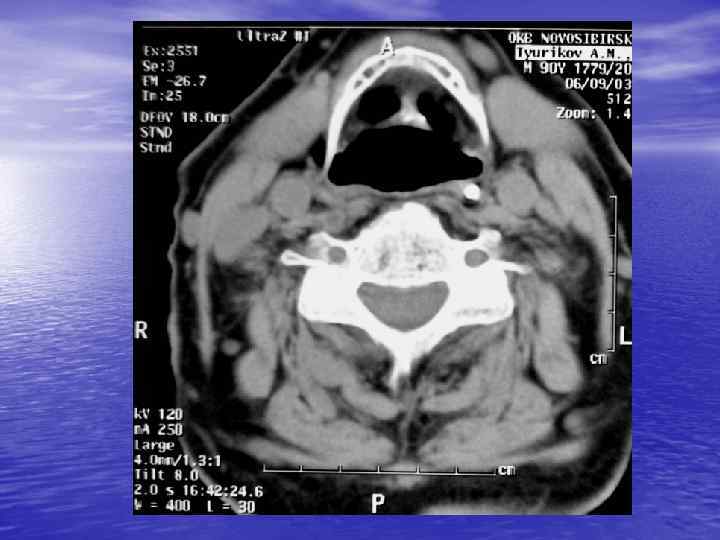

рентгенотопограмма